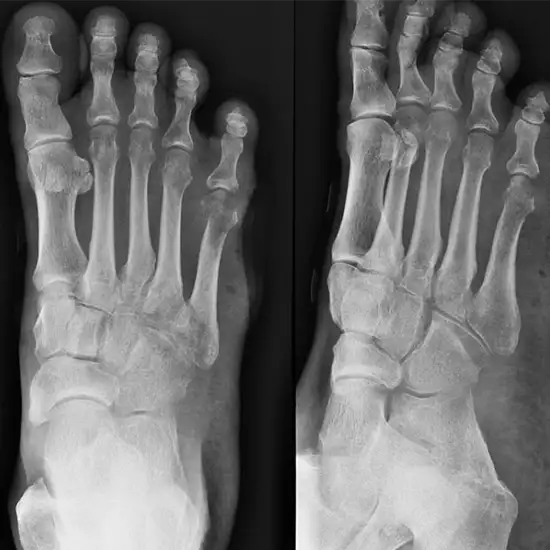

X-ray Left Toes AP & Oblique

An X-ray of the Left Toe AP Oblique View Test is a safe and painless way to determine the condition of the big toe bones and the soft tissues (skin and muscles) surrounding the toe bones using a small amount of radiation.

• * To diagnose any broken or fractured bones in the toe and monitor the healing of the damaged bone once it has been fixed.

• * To rule out any possible infection, osteoporosis, bone abnormalities, unusual bone growth, and arthritis (inflammation of the joints).